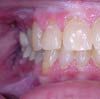

Figure 3

In adults, painful ulceration of gingival tissue that recurs in the same location suggests a secondary intraoral presentation of HSV infection--recurrent intraoral herpes (Figure 3) (the intraoral equivalent of the lip lesion). Although recurrent HSV lesions usually arise in the same location, they may occur on nongingival mucosa, especially in immunocompromised persons.3 HSV-2 also recurs intraorally,4 but not as frequently as HSV-1. A simple assessment of suspected recurrent intraoral HSV infection may be done through viral culture. Cytologic evaluation with fluorescent staining is rarely used but it may be helpful if available; antibody titers can provide additional evidence of disease. In immunocompromised persons, it may be prudent to perform cultures of any intraoral lesions for HSV, regardless of location, because early intervention helps prevent morbidity.5